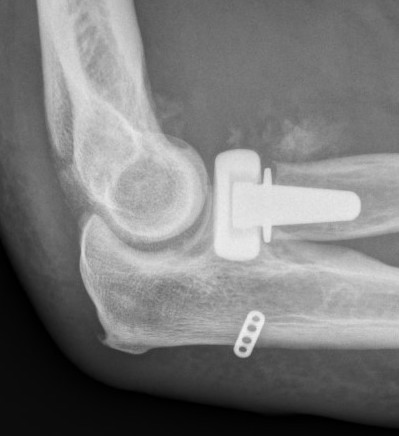

Elbow dislocation with radial head fracture

Management

Critical to elbow stability

Based upon Mason classfication

Radial head replacement + LCL repair / reconstruction +/- MCL repair / reconstruction if unstable

2. Restore radial head stability - radial head ORIF or arthroplasty

| Type II / Reconstructable radial head | Type III / Radial head arthroplasty |

Lateral / Kocher / Kaplan / EDC split approach - excise radial head - can suture small coronoid process fracture through gap - radial head replacement - LCL +/- common extensor origin repair - reassess stability

Radial head replacement with lag screw fixation of Type II coronoid

Radial head replacement with lasso fixation of small coronoid fragment